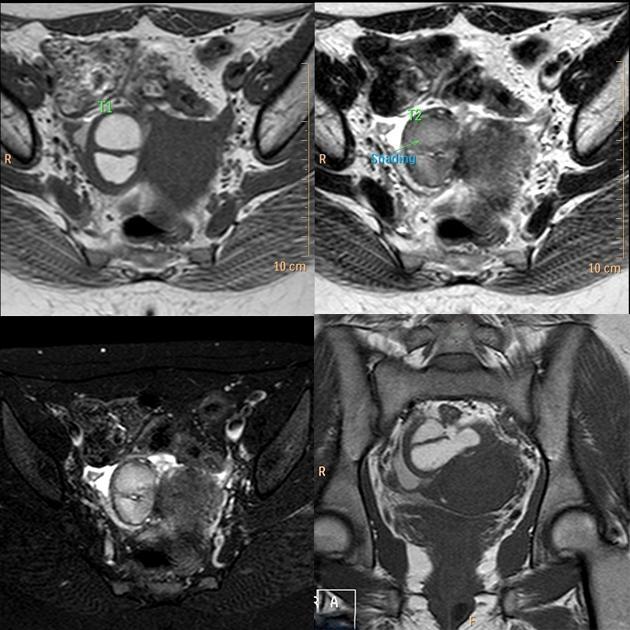

子宫内膜异位至双侧卵巢,T2WI 斜冠位和轴位双侧卵巢类圆形高低混杂信号结节,注意左侧卵巢子宫内膜异位症与乙状结肠之间线性低信号影,提示这些结构之间的粘连。

子宫内膜异位至右侧卵巢,T2WI 轴位发现右侧附件区「葫芦形」高信号,但是更应该注意的是病灶右侧带状低信号,提示与周围结构的黏连。